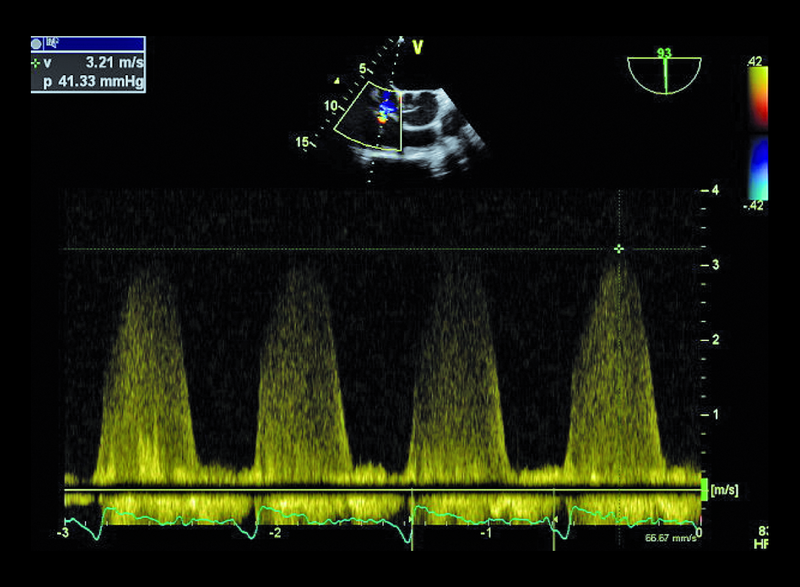

Mężczyzna, lat 68. Jakie patologie można rozpoznać na rycinach?

3. Niedomykalność zastawki trójdzielnej (ryc. 3, 4).

4. Nadciśnienie płucne (ryc. 4).